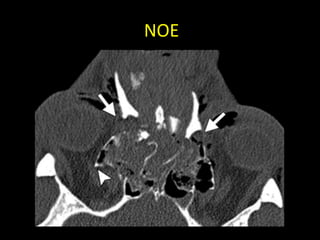

FRACTURA NASO-ÓRBITO-ETMOIDAL

(NOE)

• Golpe en nariz y transmisión posterior

etmoidal (contrafuertes maxilares mediales)

• Fractura del tercio medio facial que involucra

hueso etmoides (lámina perpendicular,

papirácea y cribiforme), propios nasales y

apófisis ascendentes de maxilares.

• Es la zona de la cara con menor resistencia a

fuerzas de fractura.

NOE

• Clasificación de Markowitz

– Tipo I: segmento central único, sin compromiso del

canto interno.

– Tipo II: segmento central conminuto, sin compromiso

del canto interno.

– Tipo III: segmento central conminuto, con

desinserción del canto interno.

FRACTURA NASO-ÓRBITO-ETMOIDAL (NOE) • Golpeen nariz y transmisión posterior etmoidal (contrafuertes maxilares mediales) • Fractura del tercio medio facial que involucra hueso etmoides (lámina perpendicular, papirácea y cribiforme), propios nasales y apófisis ascendentes de maxilares. • Es la zona de la cara con menor resistencia a fuerzas de fractura.

NOE • Clasificación deMarkowitz – Tipo I: segmento central único, sin compromiso del canto interno. – Tipo II: segmento central conminuto, sin compromiso del canto interno. – Tipo III: segmento central conminuto, con desinserción del canto interno.

• #20 comminuted fracture of the NOE complex with telecanthus and involvement of the bilateral lacrimal fossae (arrows), findings indicative of a type III fracture of the NOE complex with medial canthal tendon avulsion. A fragment of the fractured right medial orbital wall impinges on the right optic nerve